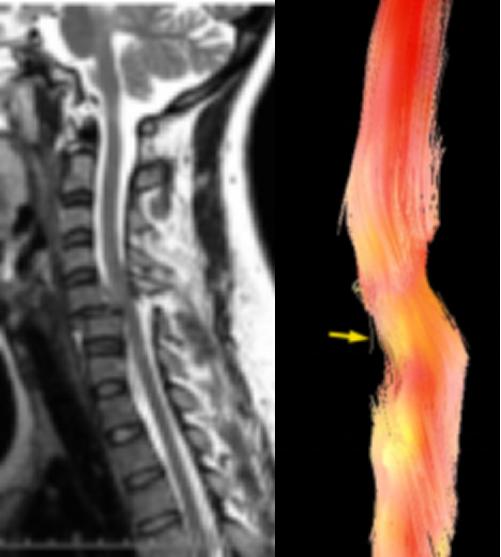

脊髓病变应用

脊髓损伤的发病率为20~40/100万,早期准确反映脊髓损伤及其程度,了解轴突损伤再生及再髓鞘化过程,对于脊髓损伤治疗及预后具有重要意义。常规MRI检查低估了脊髓损伤的程度,不能用于评估脊髓的功能状态,有关脊髓评价和治疗效果验证目前主要依靠临床的主管评价,缺乏客观的功能影像学标准。

DTI技术能敏感地反映脊髓中水分子扩散各项异性的改变,从而提供活体脊髓的细微病理生理结构变化信息,理论上认为DTI测量所得的ADC值和FA值能反映脊髓损伤和修复期轴突再髓鞘化过程,因而正应用于脊髓损伤动物模型和临床研究中。

脊髓损伤患者,显示纤维束明显扭曲、变形、部分断裂